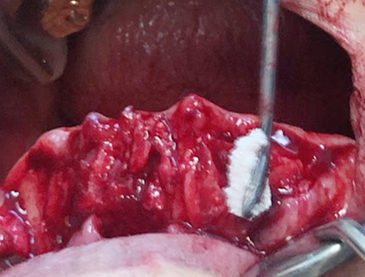

• Alveoloplasty (Posterior teeth) 2